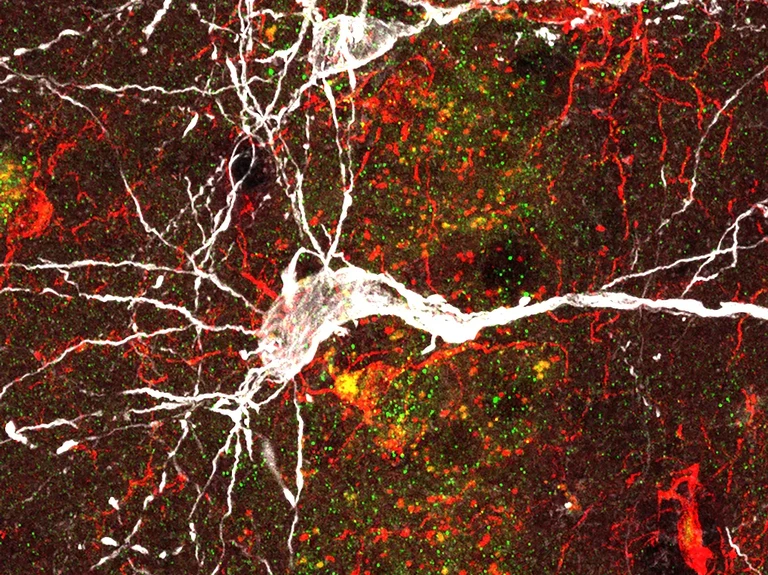

A microscopic view of a neuron (white),

surrounded by deposits of amyloid-beta protein (red). These deposits trigger neuroinflammation and thus drive progression of Alzheimer’s disease.